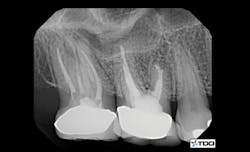

To date, endodontics is among the most necessary areas for cone beam. Another survey conducted by Clinicians Report Foundation found that most endodontists are now using cone beam. What potential problems do you see in endodontics when using a three-dimensional image? Often, a canal has been missed, such as the mesiobuccal canal in maxillary first molars. Frequently, there is another root present that is superimposed over the other roots and would be completely unidentifiable on a 2-D image (figures 1 and 2). Resorption can easily be hidden by the pulp, which is about the same level of radiolucency. Cracks in teeth can often be found by cone beam that cannot be seen with conventional 2-D radiographs.

Figures 1 and 2: Cone beam shows symptomatic maxillary second molar to have an untreated root. (Photo courtesy of Dr. Dale Miles.)